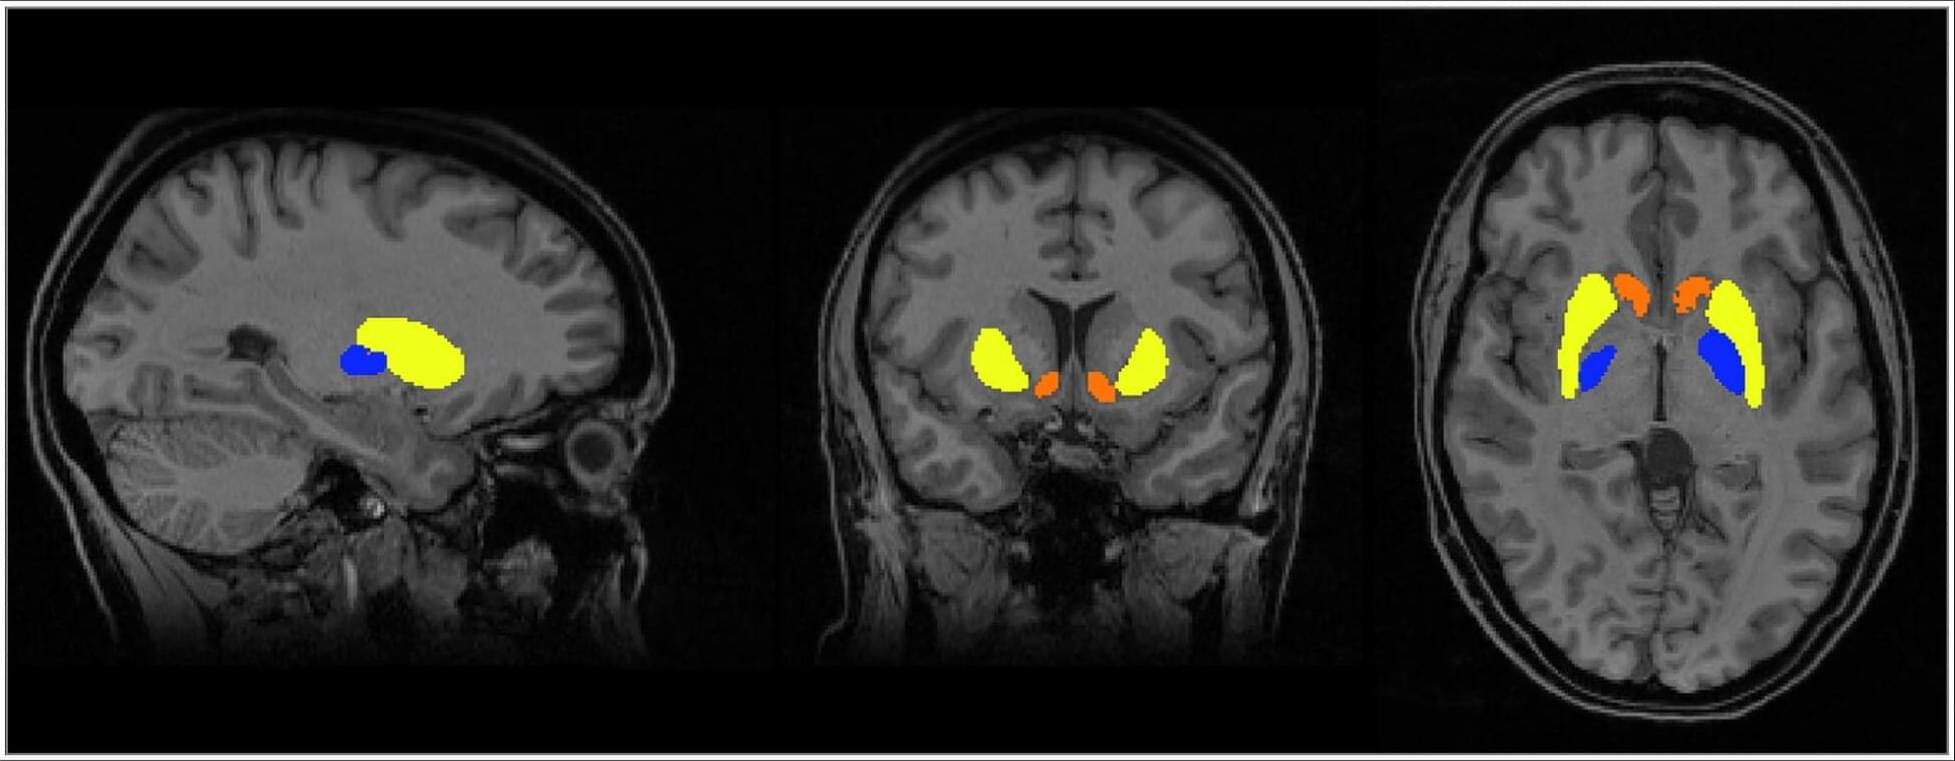

Women with a history of preeclampsia receiving usual care had smaller volumes in subcortical regions (putamen, accumbens, pallidum) than those with gestational hypertension, differences that were not observed in the intervention group.

This randomized clinical trial indicates that a postpartum blood pressure management intervention after hypertensive disorders of pregnancy may be associated with favorable brain structure during the first year post partum. The intervention was linked to larger white matter volumes across women with hypertensive pregnancy (gestational hypertension and preeclampsia). In addition, women with a history of preeclampsia in the usual care arm showed smaller subcortical brain volumes at 6 to 9 months post partum than those with gestational hypertension; these differences were not evident among women in the intervention arm.